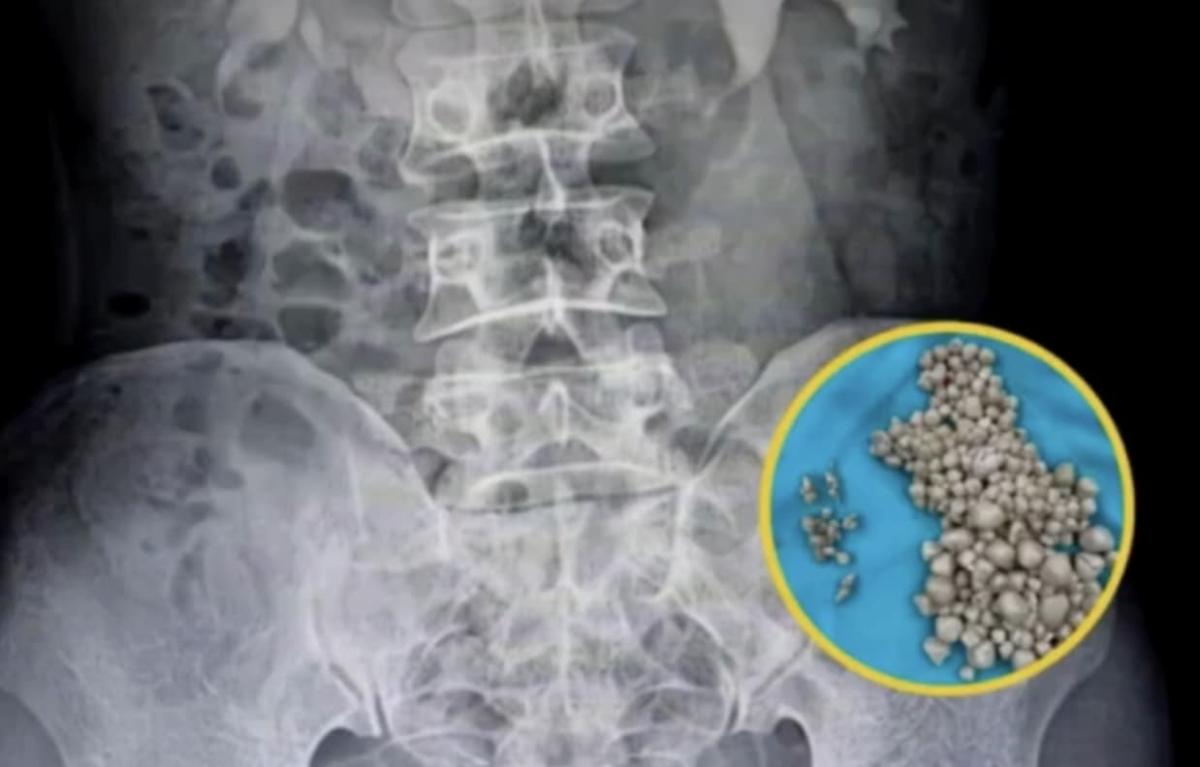

Μια 20χρονη γυναίκα, επισκέφθηκε το νοσοκομείο, νομίζοντας ότι έπασχε από απλό πυρετό και έντονους πόνους στη μέση. Αντί γι’ αυτό, οι γιατροί ανακάλυψαν πως το νεφρό της ήταν γεμάτο με περισσότερους από 300 πέτρες — τόσους πολλές, που ένας γιατρός το παρομοίασε με ταψιά γεμάτα μικρά ψωμάκια ατμού.

Η νεαρή γυναίκα άρχισε να νιώθει έντονη κόπωση, πυρετό και πόνους στη μέση. Οι γιατροί αρχικά υποψιάστηκαν λοίμωξη του ουροποιητικού ή φλεγμονή των νεφρών — καταστάσεις που αντιμετωπίζονται εύκολα. Όμως οι αξονικές και υπερηχογραφικές εξετάσεις αποκάλυψαν κάτι απίστευτο: το δεξί της νεφρό ήταν διογκωμένο και φραγμένο με εκατοντάδες πέτρες σαν μεγάλους κόκκους άμμου σχεδόν δύο εκατοστών.

Οι περισσότεροι ασθενείς έχουν έναν ή δύο πέτρες. Η νεαρή αυτή γυναίκα είχε εκατοντάδες, που συσσωρεύονταν επί χρόνια λόγω αφυδάτωσης, μέχρι που το σώμα της κατέρρευσε. Οι πέτρες είχαν μπλοκάρει το σύστημα διήθησης των νεφρών, προκαλώντας λοίμωξη και πυρετό.

Οι χειρουργοί του νοσοκομείου πραγματοποίησαν περκοτανοσκοπική νεφρολιθοτομή, μια ελάχιστα επεμβατική διαδικασία μέσω μικρής τομής στην πλάτη. Σε διάρκεια περίπου δύο ωρών, αφαίρεσαν περισσότερους από 300 πέτρες γεμίζοντας πολλούς ιατρικούς δίσκους.

Oι πέτρες που αφαιρέθηκαν από τα νεφρά της νεαρής κοπέλας

H ακτινογραφία με τις πέτρες πάνω αριστερά